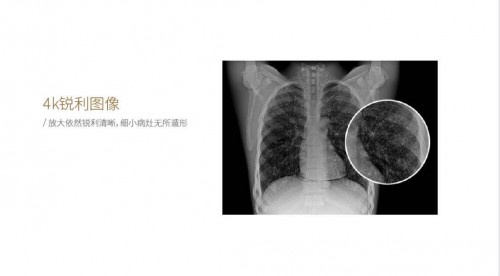

作为国产首款百微平板DR——新东方1000F系列高端产品,能够快速、高清且低剂量成像,更早发现细微病灶,助力高效精准诊疗。 中国智造100微米平板,高清成像

平板是X光产品中最为核心的部件。 100微米平板探测器, 采集数据量巨大的图像细节,可将细节检测能力提升30%。搭载高速图像处理平台,运用极限成像技术,大幅提升图像处理速度,缩短图像处理时间,其卓越的细节探测和显示能力,可增强对肋骨骨骼和肺纹理细节处理、对骨骼和软组织细节处理,能够满足骨科、儿科等对细节成像更精细的需求,满足对成像细节高标准的需求。 十轴联动六向跟踪操控无限智能